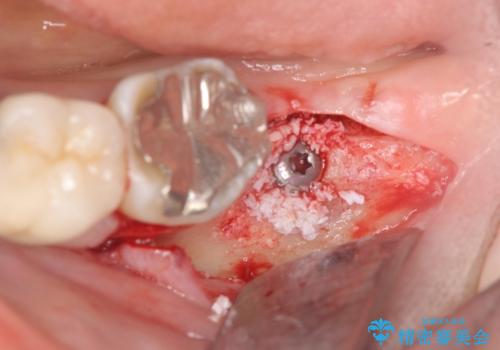

今後の機能回復方法としてインプラント治療を希望されたため、将来的に大規模な骨造成が必要とならないよう歯槽堤保存術を抜歯と同時に行いました。

良好なインプラントの植立を行うためには、十分な骨量があることが必須条件です。

術前、歯の破折により大きな骨の吸収が認められていたため骨量を十分に回復するために抜歯と同時に歯槽堤保存術を行い十分な骨量の回復をすることができました。